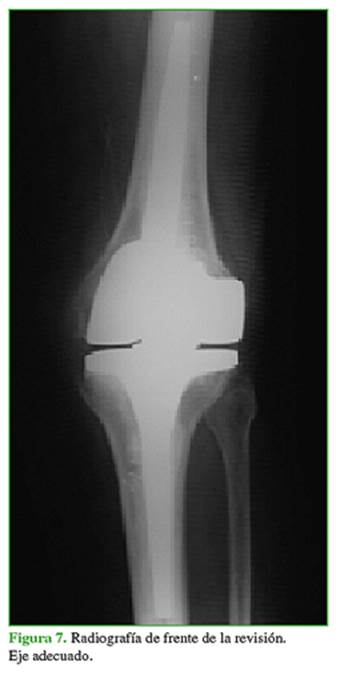

Durante la cirugía, se detectó la rotura del poste central del inserto de polietileno (liner) (Figura 5). Se procedió a retirar la prótesis primaria para luego implantar una prótesis abisagrada con plataforma rotatoria (Endo-Model NR®, Waldemar Link GmbH & Co. KG, Hamburgo, Alemania), con buena evolución hasta la fecha (15 meses después de la cirugía) (Figuras 6 y 7).